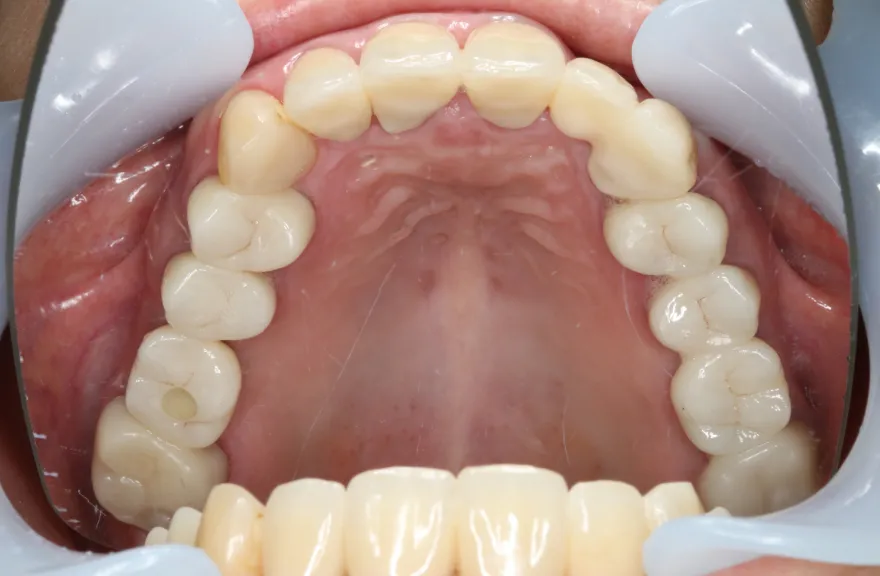

上顎は5本の歯を保険のブリッジ治療で連結してある状態でした。どの歯の状態も良くなく、今回なんとか治療を行ったとしても近いうちに再びトラブルを起こしてくることが予想されました。

下顎は9本の歯が残っており、虫歯はあるものの差し歯として使える状況でした。

しかし、患者さんとの話し合いの中で、「数年前に行った治療なのに再び全てやりかえないといけないのは単純にしんどい。もうやりかえのないようにしたい」という患者さんの強い思いが伝わってきました。

今回で完全に治療をやり切ってしまい、今後は最小限の介入で歯科と付き合えるよう、上下顎残っている歯の全ての抜歯、必要な本数のインプラント埋入、上顎は総義歯形態で対応することとしました。 - 治療のリスク